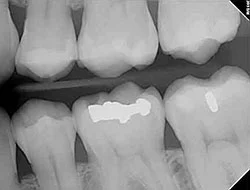

Because our practice is dedicated to providing you with the safest and most convenient treatment options available, we utilize advanced digital X-ray technology in our office.

Digital X-rays provide several advanced imaging options designed to save time, provide clearer dental photos, and expose patients to less radiation than traditional X-ray technology.